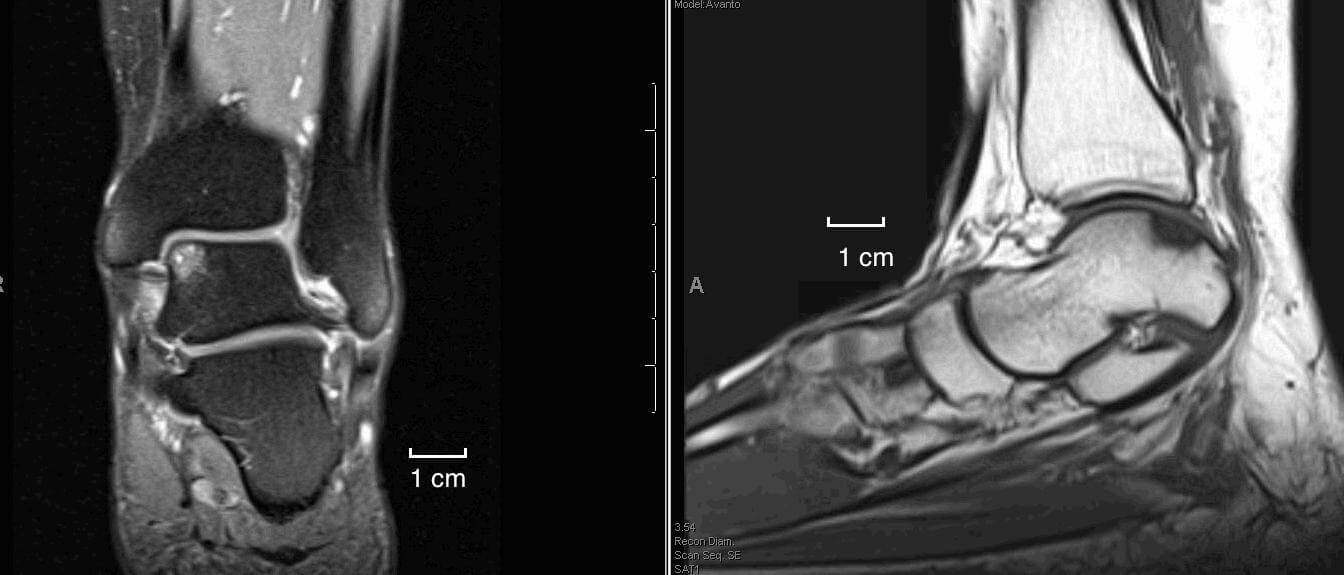

Several factors must be considered to decide to treat joint cartilage injury: surface area, depth, location, history, associated injuries, knee stability, meniscal injuries, mechanical limbs, patient age, and last but not least functional characteristics of the patient. MRI examination, Outerbridge Classification, ICRS Assessment System are very useful for choosing the therapeutic method. Regarding the repair of cartilage lesions along with the entire thickness, several treatments have been suggested, but none have been identified as the "gold standard" to allow the reproduction of normal hyaline joint tissue. One of the first treatments is simple abrasive chondroplasty when the cartilaginous defect is "shaved" and subjected to extensive debridement.